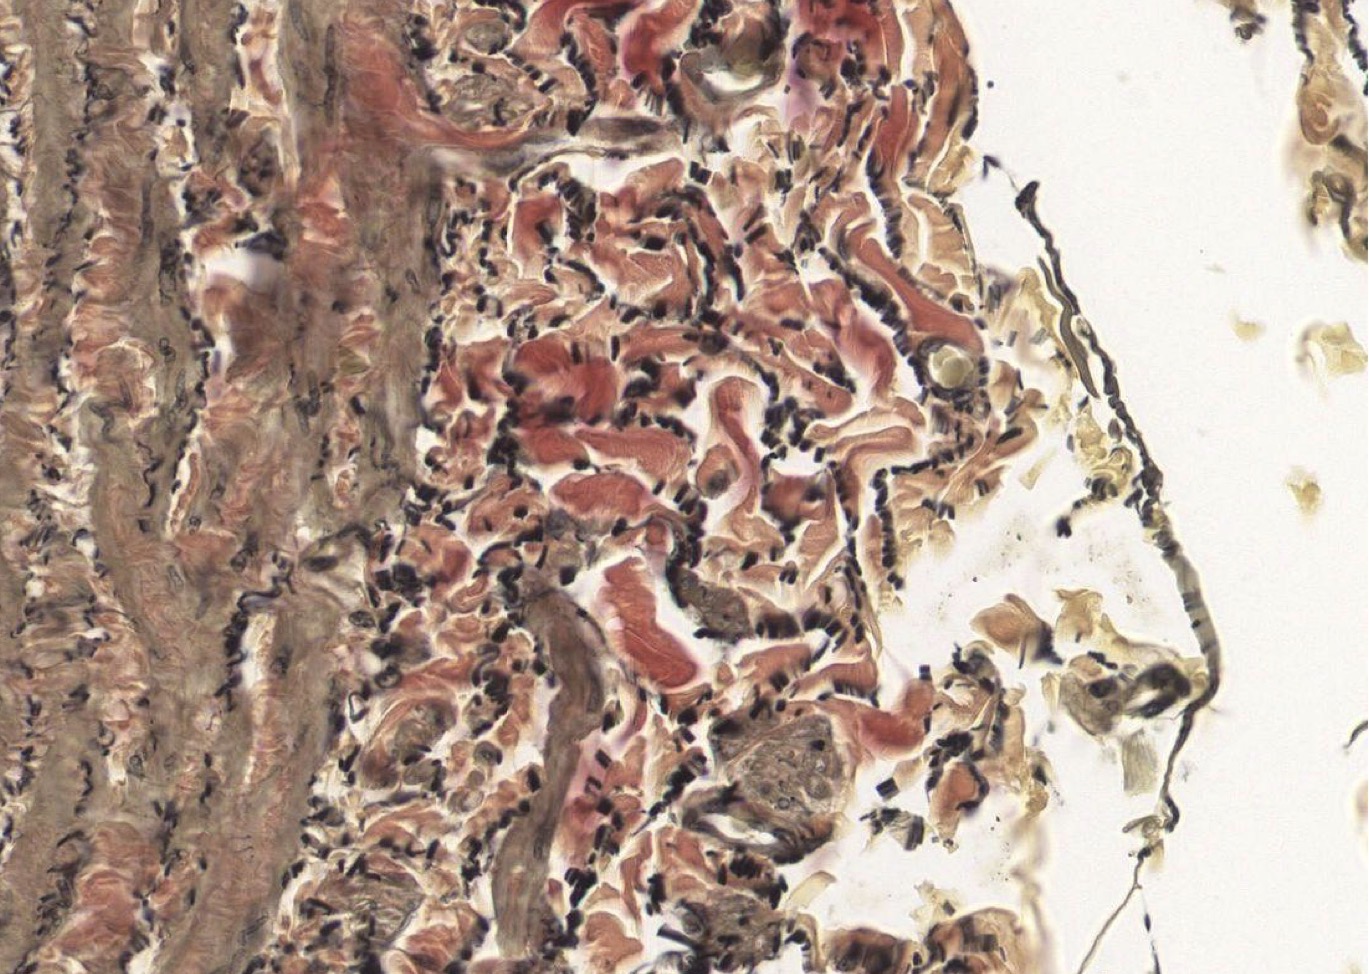

I = Epicardium in Ventricle.

Outer mesothelial (simple squam epit) cells missing, supported by DICT on outside and has Loose Unilocular Adipose CT.

Identify Which partition this is and Where?

I = Epicardium (right side) and Myocardium (Left) in Atrium.

Outer mesothelial (simple squam epit), supported by DICT.